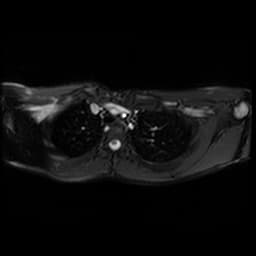

Cộng hưởng từ tim (CMR)

CMR là phương pháp lựa chọn để đặc trưng hóa mô toàn diện và đánh giá chức năng [3].

Giải phẫu và cường độ tín hiệu: Chuỗi xung T1-weighted máu đen (black-blood) rất tốt để quan sát màng ngoài tim dày và giảm tín hiệu [1]. Chuỗi xung T2-weighted có thể phát hiện phù nề, gợi ý thành phần viêm đang hoạt động.

Ngấm thuốc Gadolinium muộn (LGE): LGE được sử dụng để xác định tình trạng viêm màng ngoài tim đang hoạt động. Sự ngấm thuốc của màng ngoài tim gợi ý rằng tình trạng co thắt có thể đảo ngược bằng liệu pháp kháng viêm thay vì phẫu thuật [1].

Cine MRI: Các chuỗi xung cine thời gian thực có thể cho thấy dấu hiệu "septal bounce" (vách liên thất nảy nghịch thường), một sự di chuyển đột ngột của vách liên thất về phía thất trái trong khi hít vào, đây là dấu hiệu đặc trưng của sự phụ thuộc lẫn nhau giữa hai thất.

CMR Tagging: Kỹ thuật chuyên biệt này có thể phát hiện các dính kết giữa các lớp màng ngoài tim và cơ tim bằng cách cho thấy sự thiếu hụt hiện tượng "trượt cơ tim" trong chu kỳ tim [1].

Đánh giá cơ tim: CMR cũng được sử dụng để loại trừ teo cơ tim hoặc xơ hóa cơ tim trước khi lập kế hoạch phẫu thuật cắt màng ngoài tim [1].